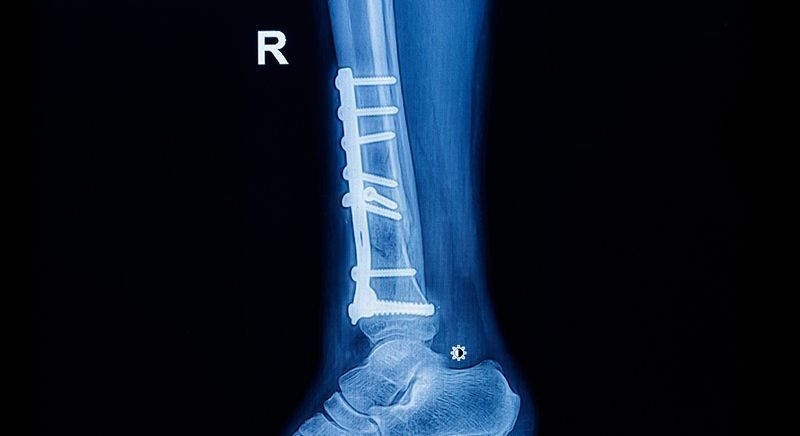

Patología y cirugía traumática

Venga a nuestro centro de traumatología para tratar de manera integral las fracturas que pueda tener. Nosotros utilizamos abordajes percutáneos y una serie de técnicas de rehabilitación que están orientadas a que el paciente se recupere en el menor tiempo posible. Somos especialistas en trauma complejo y eso también incluye las fracturas de columna, de pelvis y de acetábulo.